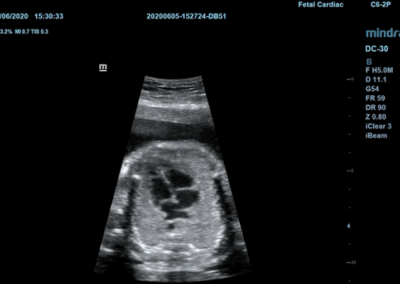

Los sistemas ecográficos estándares disponibles en la actualidad generalmente permiten un diagnóstico básico, pero carecen de funcionalidades avanzadas. Ahora, el DC-30 FullHD es la respuesta perfecta para un rendimiento de imagen de alta calidad, con una pantalla táctil de 21,5 pulgadas y funciones avanzadas como Auto IMT, iScape, elastografía Natural Touch, imágenes con contraste UWN e imágenes Doppler tisulares en el ámbito de las imágenes generales, y Smart OB, Smart face e iLive en el ámbito de la obstetricia.